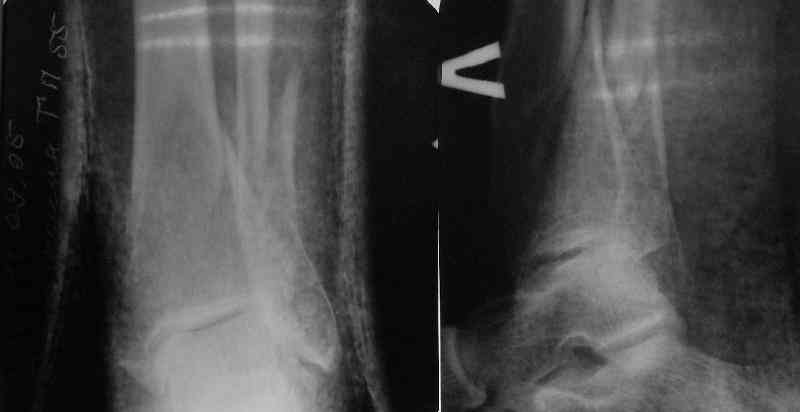

I am just trying to illustrate that prevention of 1)tibial valgus and 2)loss of reduction can be provided without fibular plating. Small changes of conventional nailing techniques allow to maintain reduction of the tibia reliably without adjunctive fibular stabilization.

In delayed cases acute length restoration performed only in the tibia may leave the fibula shortened thus change the mortise. So it is reasonable to restore length of both bones simultaneously by distractor and fix the fibula not with open reduction and plating but just by a single perQ screw. Example attached.